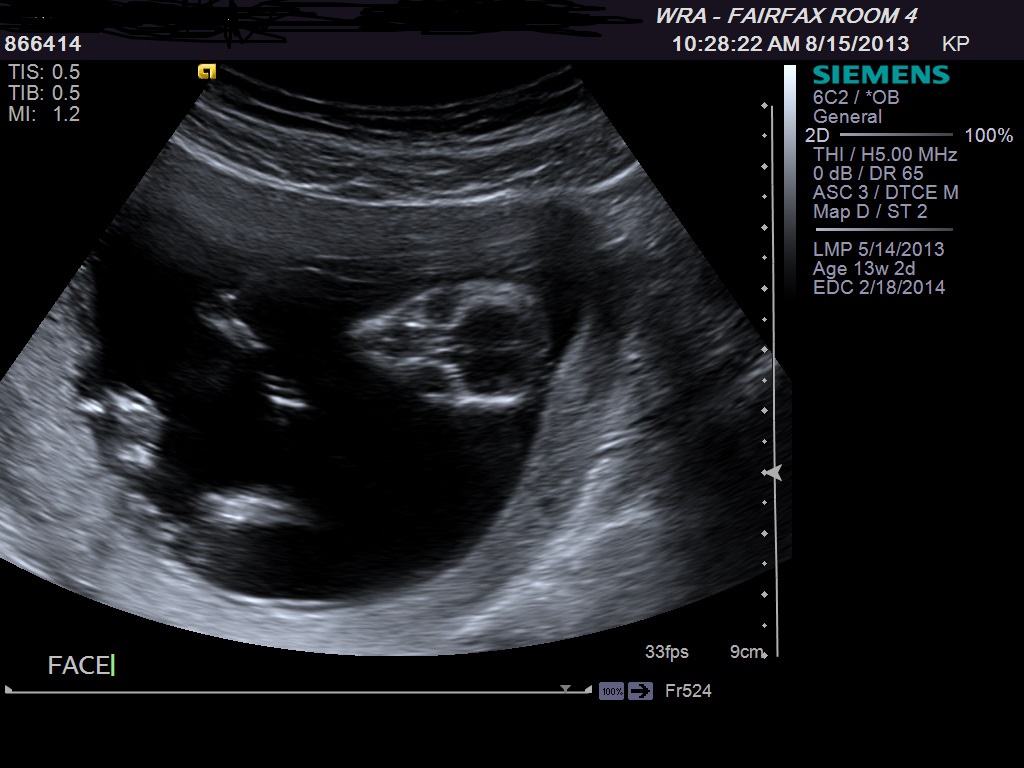

I have to go to library to post my ultrasound, and I cant wait till my nex appt Oct to know if its a boy or Girl. Please Can you guess from ultrasound i am oposting hereAttachment 13979Attachment 13980Attachment 13981

Looks girly - congrats! x